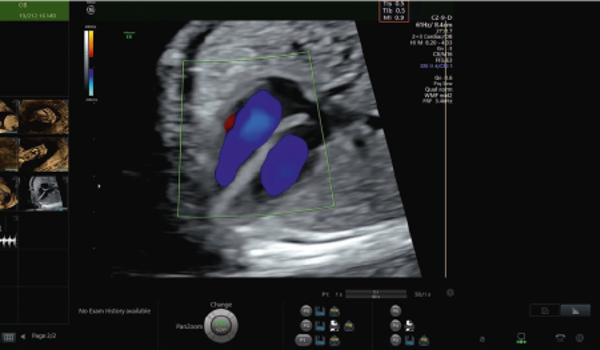

A particular focus for the group has been understanding the interplay of ultrasound device design (physics), clinical acquisition, and downstream image analysis and computer vision. Much of our recent work has concerned machine learning in ultrasound. We are interested in answering questions such as why is ultrasound scanning and interpretation hard to learn? How can we get computers to mimic what a skilled sonographer can do? What is the role of multi-modal analysis (such as eye-tracking and ultrasound video) in ultrasound imaging? And can ultrasound be simplified (assisted by AI-assistive technologies) so that minimally trained clinical professionals can use it in non-traditional healthcare settings. Our research is motivated by unmet important clinical needs in developed world and developing world settings and involves inter-disciplinary translational research collaborations with clinical groups from the UK and overseas.